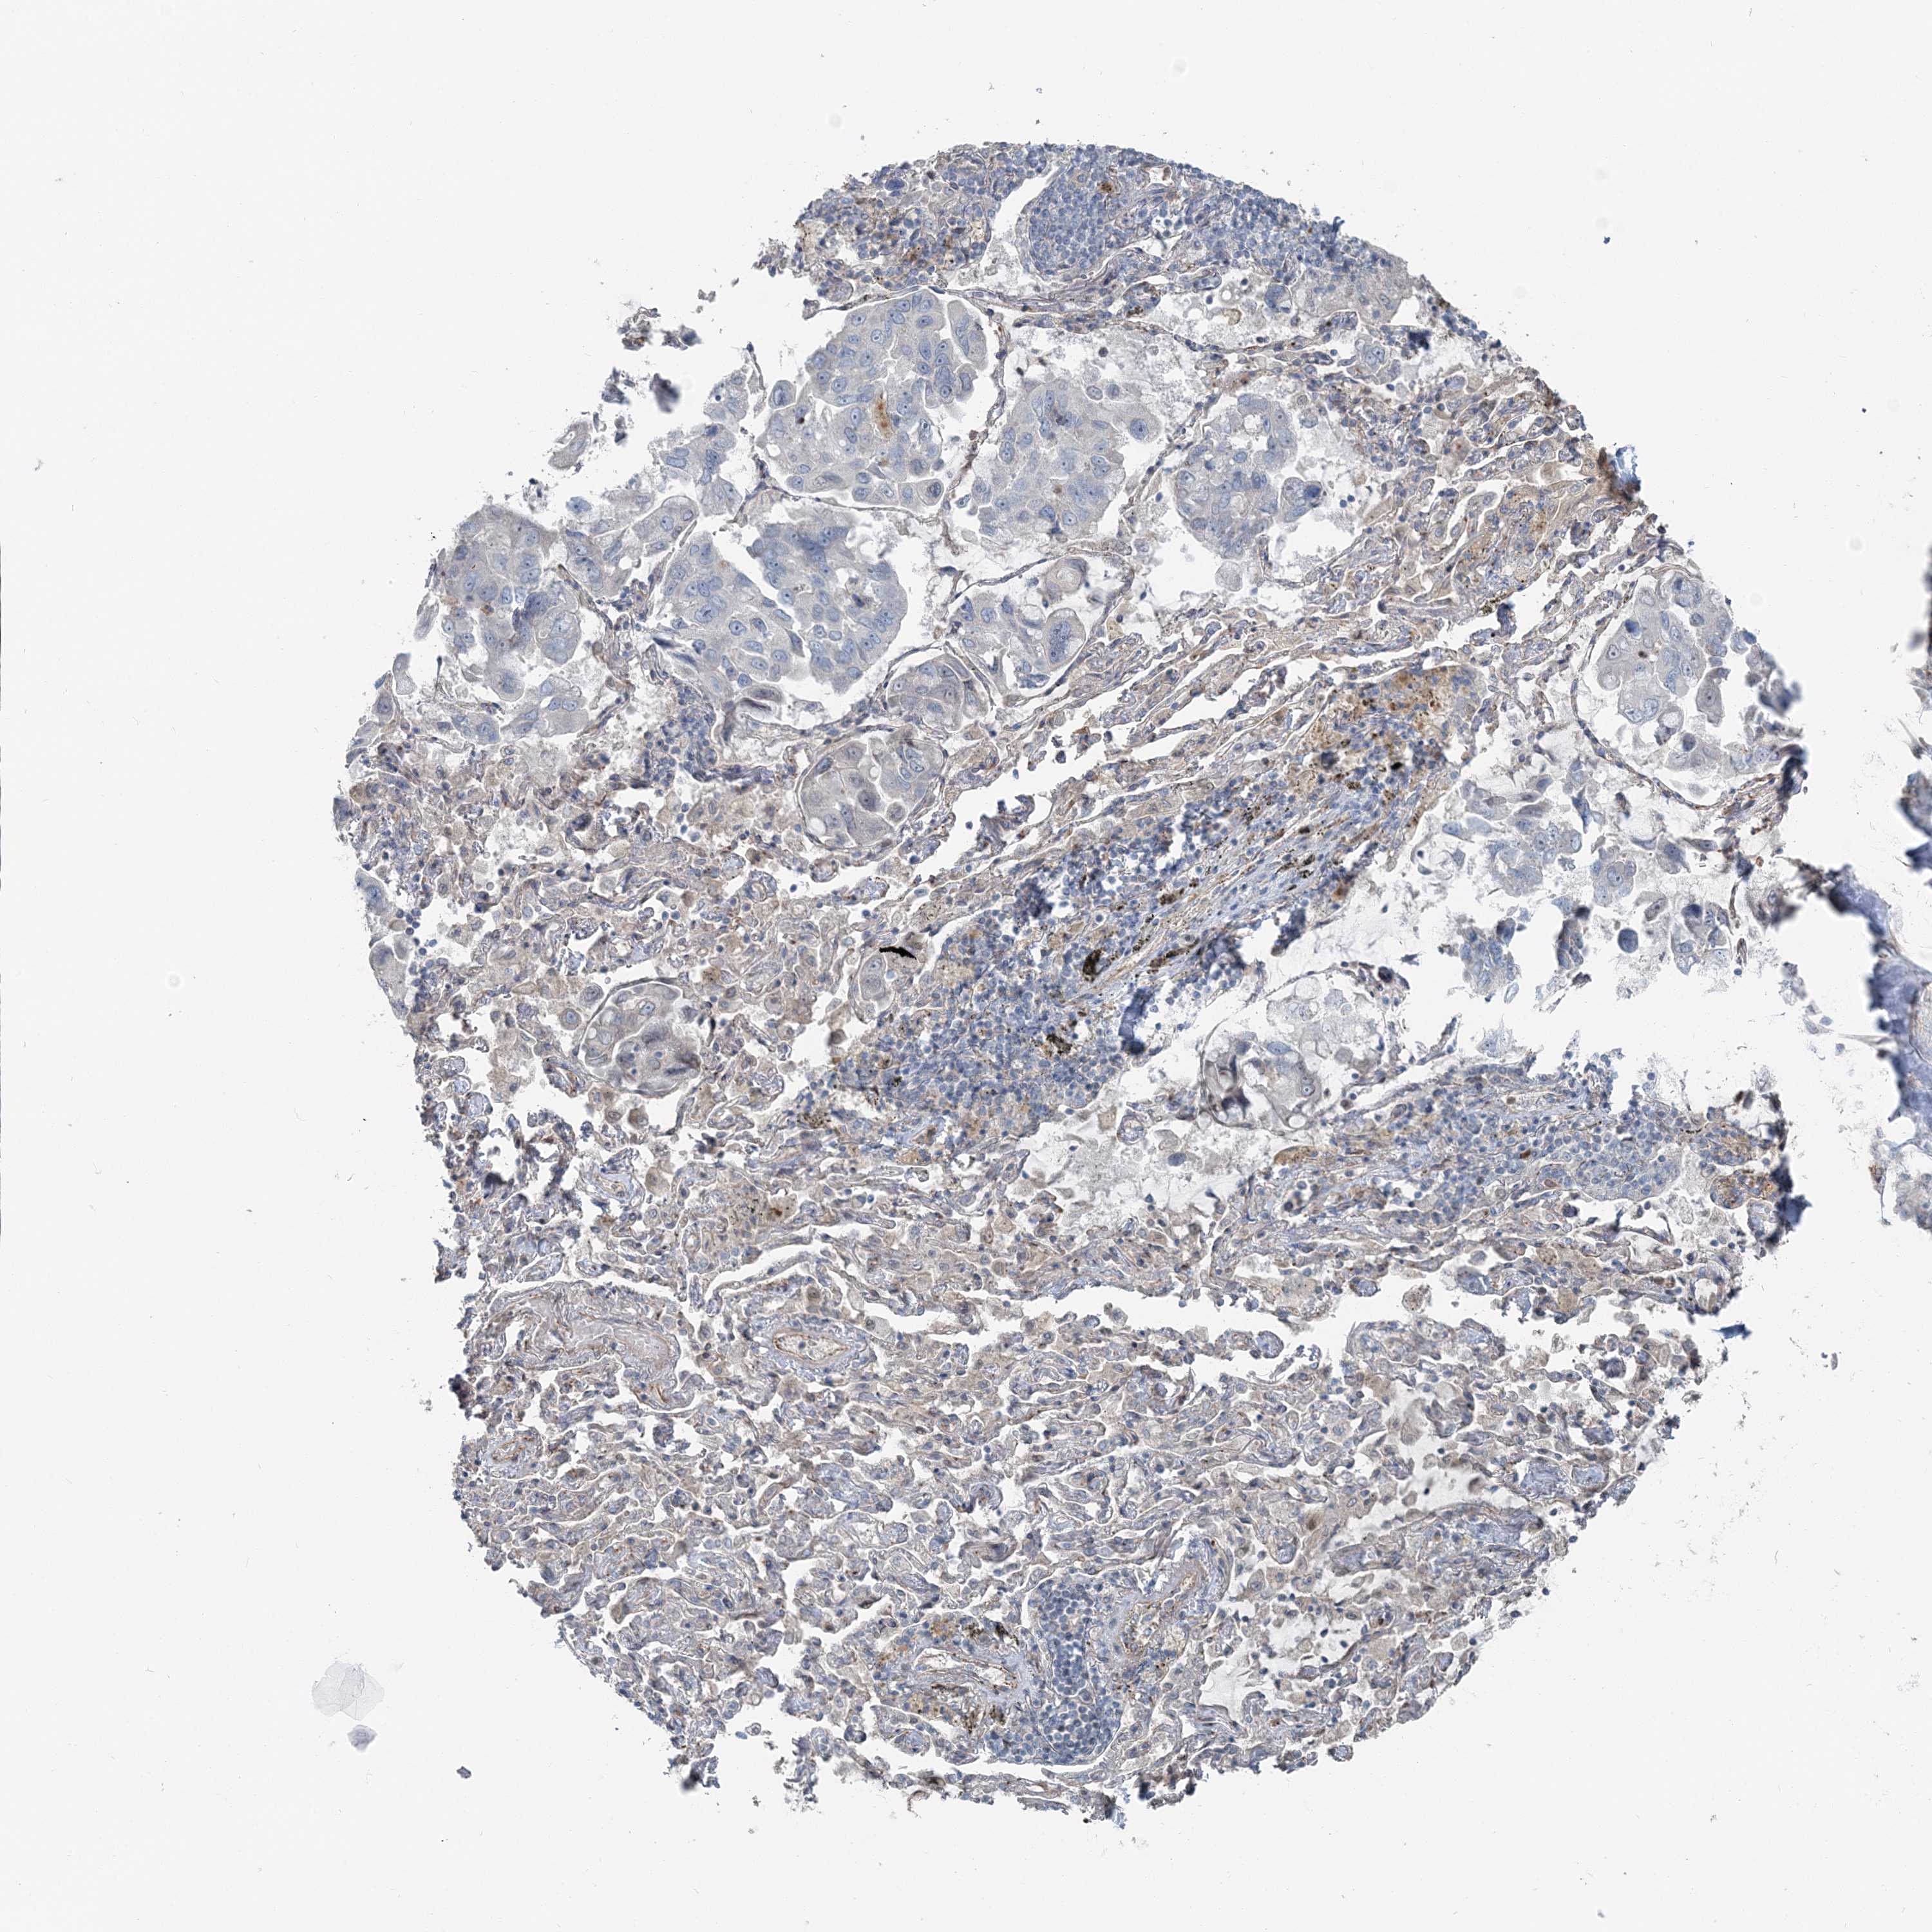

CANCER LUNG CANCER Show tissue menu

LUAD TCGA LUAD VALIDATION LUSC TCGA LUSC VALIDATION PROTEIN LUAD CPTAC PROTEIN LUSC CPTAC PROTEIN EXPRESSION

ANTIBODIES

AND

VALIDATION